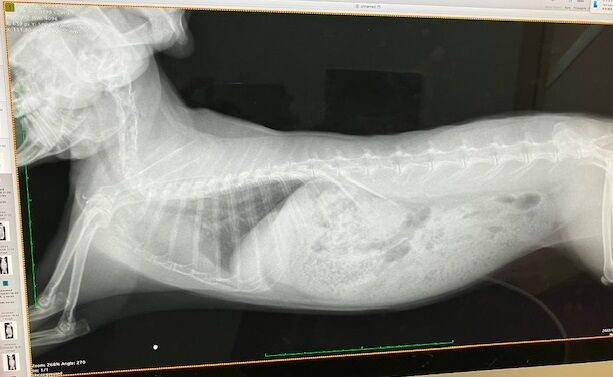

レントゲンでは...

歯根の問題はなさそうですが、鼻の奥の方(?)

堆積物か何か、何かがあるかもしれない、みたいな話でした。

どこかすぐ忘れるから指さし撮影(^_^;)

鼻涙管の通り道ではないので、排除となると外部から穴をあけるらしい…。

詳細はCTなどを用いて調べられる。

まあ、強いていえば、という感じでしたし、ひとまず経過観察です。